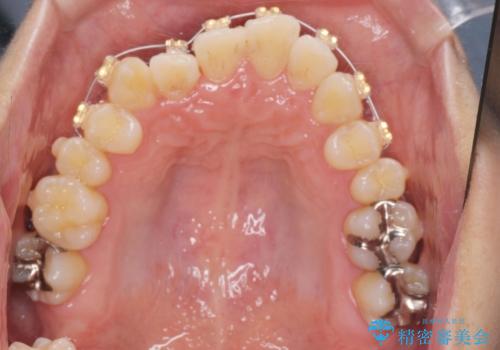

- インビザライン +部分ワイヤー矯正

すれ違いを治すのが得意な前歯部の部分ワイヤーを用いることで、治療期間を短縮することができました。